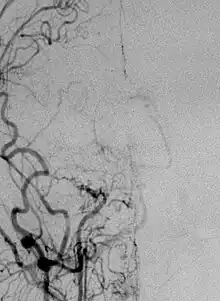

Angiogram of carotid artery of patient with moyamoya.

- (medicine) A disease in which certain arteries in the brain are constricted.